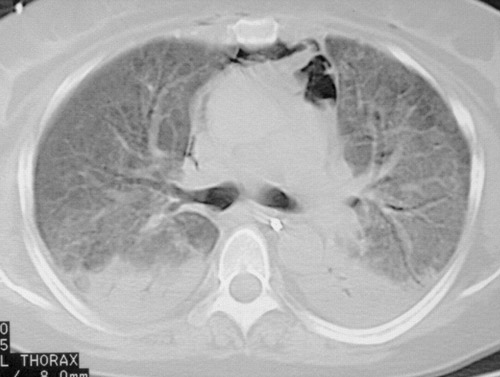

- КТ высокого разрешения. Помогает уточнить распространенность поражения легочной ткани, оценить стадию, активность и темпы прогрессирования фиброзного процесса.

КТ ОГК. Интерстициальная пневмония, участки «матового стекла» (красная стрелка) и ретикулярные изменения.